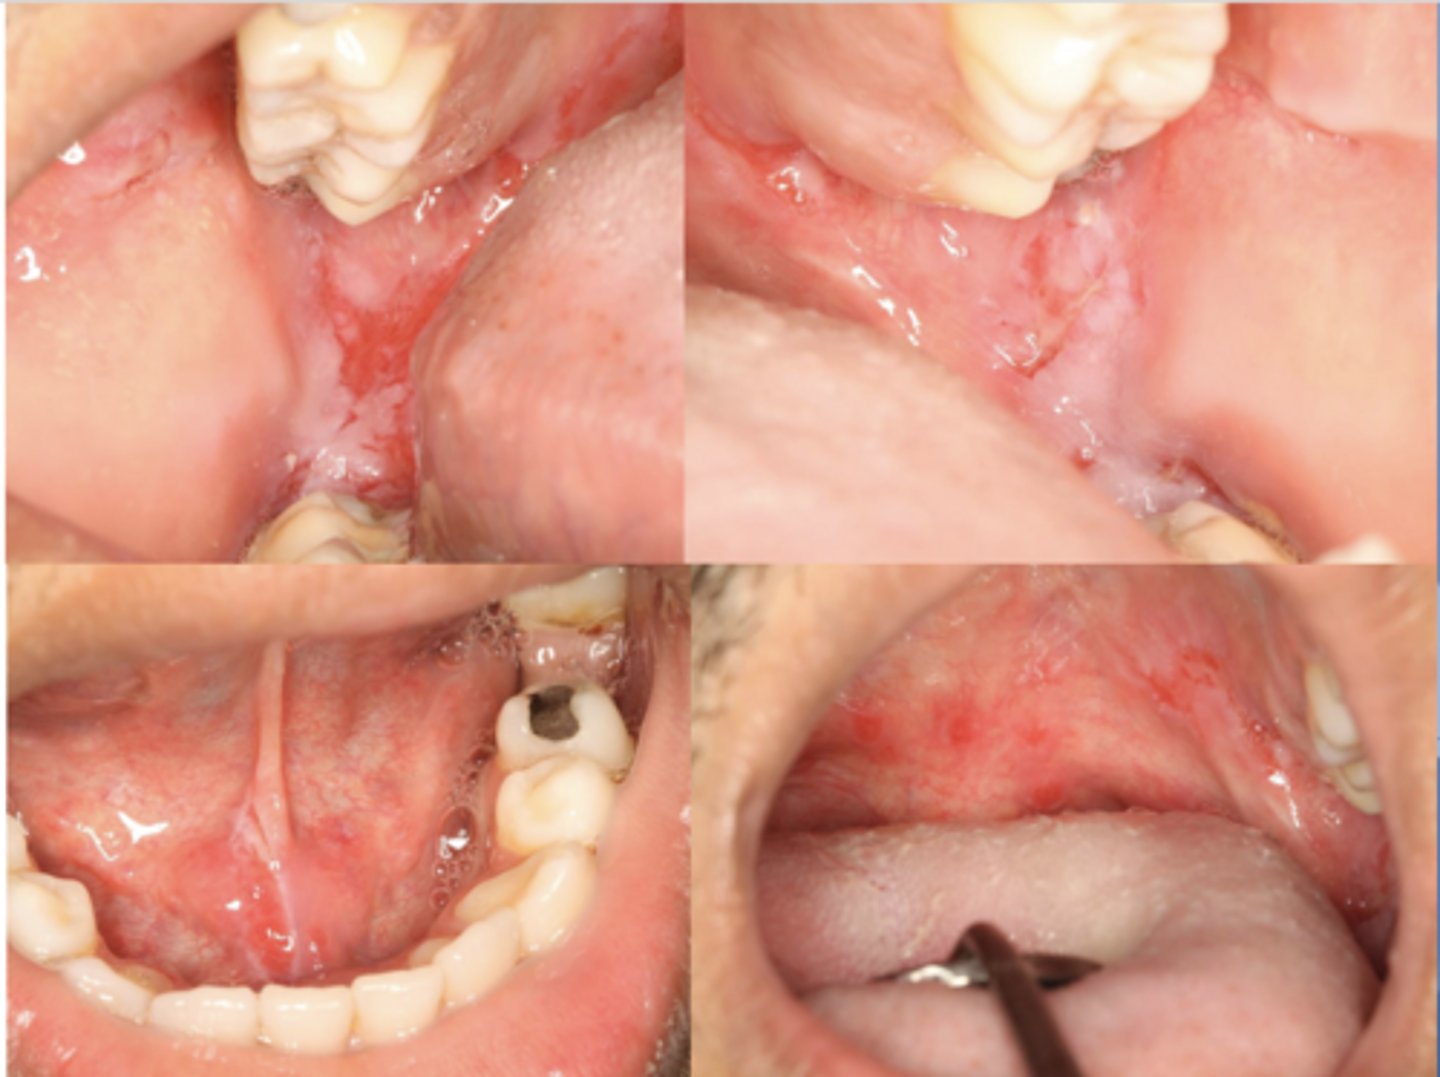

This is the clinical manifestation of which condition?

desquamative gingivitis

What condition?